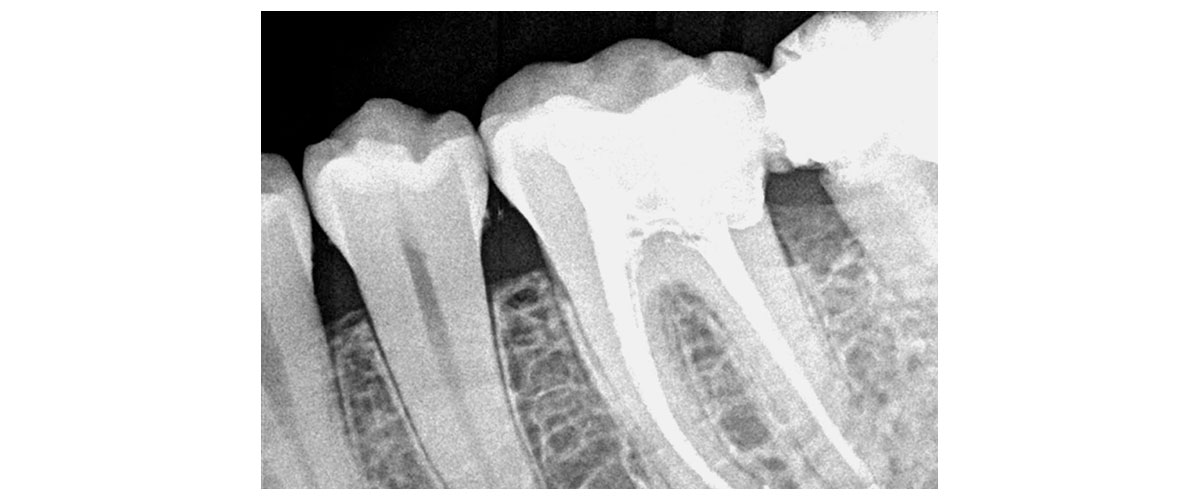

El odontólogo empezará por la realización de una completa anamnesis, un exhaustivo análisis clínico, se te solicitaran estudios (tal vez solo una panorámica, tal vez una tomografía computada, tal vez una resonancia magnética según lo que se desprenda del análisis clínico) y sobre la base de un correcto diagnóstico trabajaremos en conjunto con otros profesionales en el tratamiento y resolución de este trastorno para que puedas controlarlo y tal vez no erradicarlo de tu vida en una primera instancia pero al menos evitar que te genere serios daños.

ENDODONCIA MECANIZADA

Los históricos TRATAMIENTOS DE CONDUCTOS afortunadamente ya no son lo que eran. Muchos pacientes han pasado malas experiencias asociándolos con el dolor, sesiones largas, infecciones que no se resolvieron y piezas dentarias que terminaron perdiéndose.

En la actualidad contamos con más y mejores recursos para poder realizar una endodoncia exitosa y de ésta forma salvar una pieza dentaria que sufrió una caries grande o una fractura (que son las causas más comunes por las cuales realizamos este tratamiento).